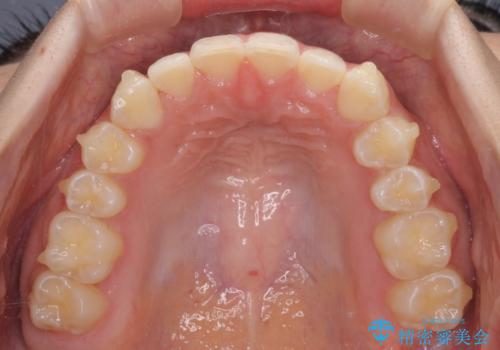

- 前歯の叢生と、奥歯の咬み合わせの悪さを気にして来院された患者様です。

左下には後続永久歯の欠損した乳歯が残存しており、叢生を相まって咬合関係が乱れていました。

乳歯は抜歯し、インビザラインにて矯正治療を行いながら、並行してインプラントによる補綴治療を行うこととしました。

矯正治療が終わるタイミングに合わせてインプラントの埋入を行っていたので、矯正治療を終了すると同時にセラミック補綴治療を行えました。

短期間でしっかりと治療を終えることができました。